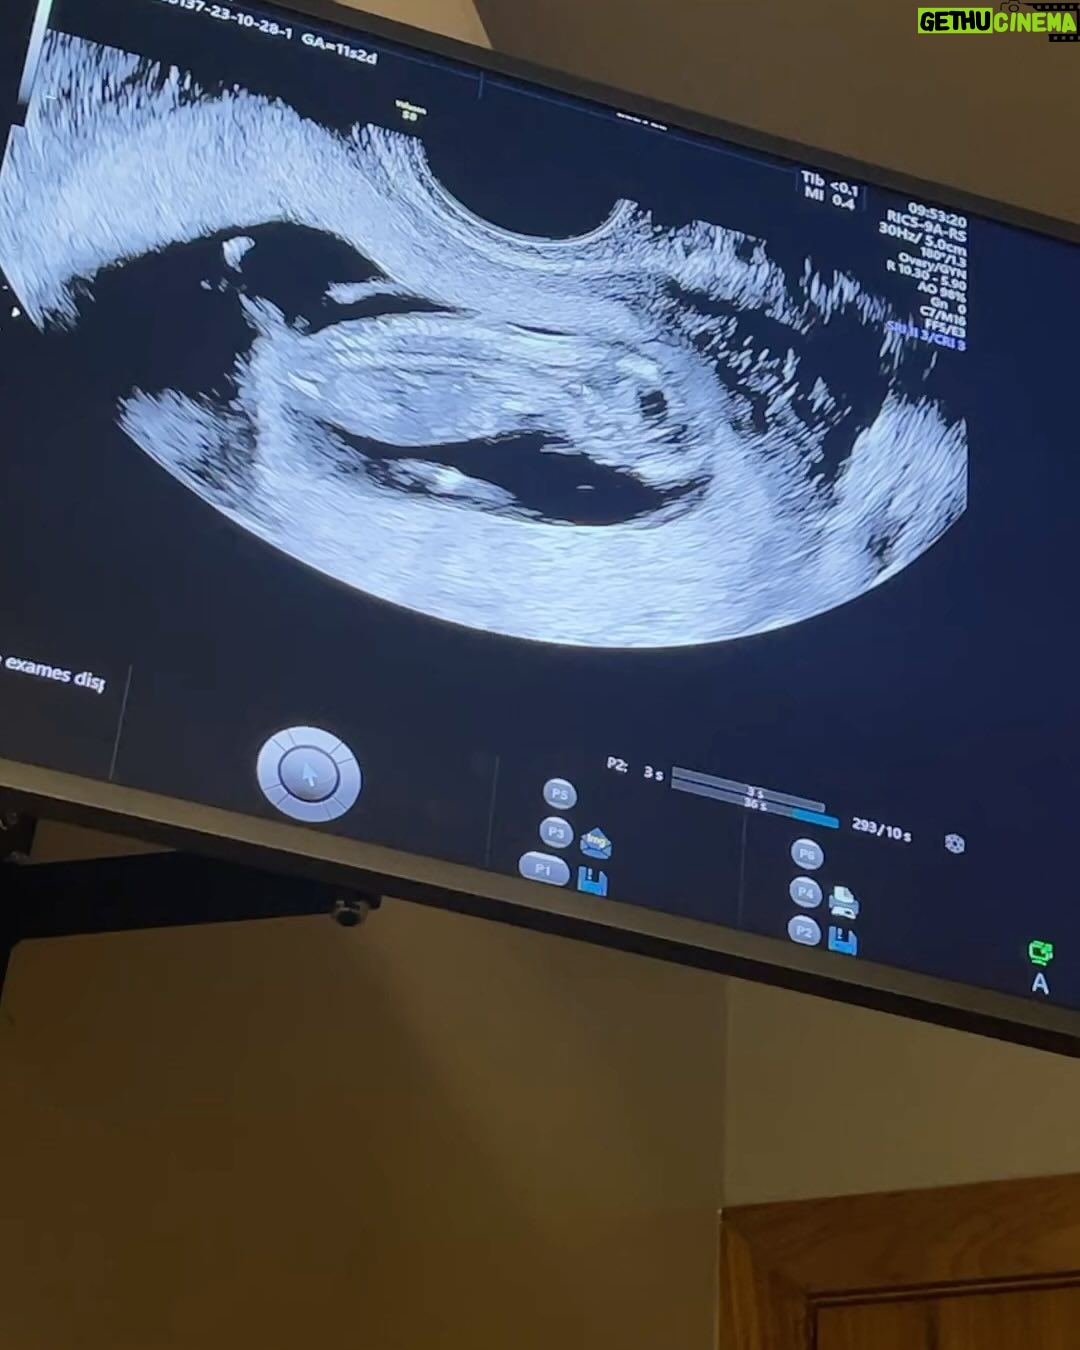

365.9K Likes – André Coelho Instagram

Caption : Mural de família das 12 semanas🤰🏻Likes : 365867

365.9K Likes – André Coelho Instagram

Caption : Mural de família das 12 semanas🤰🏻Likes : 365867

365.9K Likes – André Coelho Instagram

Caption : Mural de família das 12 semanas🤰🏻Likes : 365867

365.9K Likes – André Coelho Instagram

Caption : Mural de família das 12 semanas🤰🏻Likes : 365867

365.9K Likes – André Coelho Instagram

Caption : Mural de família das 12 semanas🤰🏻Likes : 365867

298K Likes – André Coelho Instagram

Caption : Sábado vendo as crianças 🥹🥰 e aiiiii, meninos ou meninas? 💙🩷Likes : 298035

298K Likes – André Coelho Instagram

Caption : Sábado vendo as crianças 🥹🥰 e aiiiii, meninos ou meninas? 💙🩷Likes : 298035

298K Likes – André Coelho Instagram

Caption : Sábado vendo as crianças 🥹🥰 e aiiiii, meninos ou meninas? 💙🩷Likes : 298035

298K Likes – André Coelho Instagram

Caption : Sábado vendo as crianças 🥹🥰 e aiiiii, meninos ou meninas? 💙🩷Likes : 298035

298K Likes – André Coelho Instagram